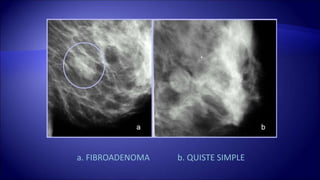

a. FIBROADENOMA b. QUISTE SIMPLE

MX: NODULO DEBORDES DEFINIDOS US: QUISTE SIMPLE

• 93.

MX: NODULO BIENDEFINIDO US: FIBROADENOMA

a. FIBROADENOMA b.QUISTE SIMPLE